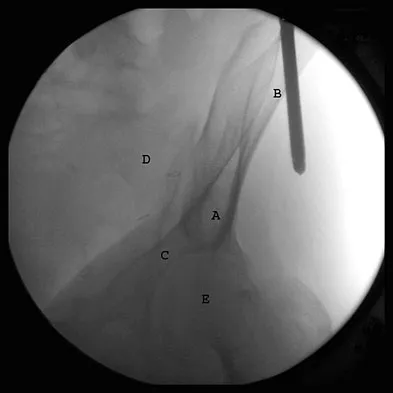

The correct starting point for an external fixation half pin placed into the anterior inferior iliac spine (AIIS) is labeled by what letter in Figure 3?